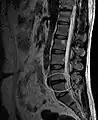

L'imagerie par résonance magnétique peut montrer la hernie, le canal vertébral, les nerfs, les tissus environnants. Les tissus mous sont les mieux analysés par cet examen qui est le plus performant pour le diagnostic de hernie discale. Les images pondérées en T2 montrent clairement la hernie.

IRM lombosacrée sagittale montrant une hernie discale de niveau L4-L5.